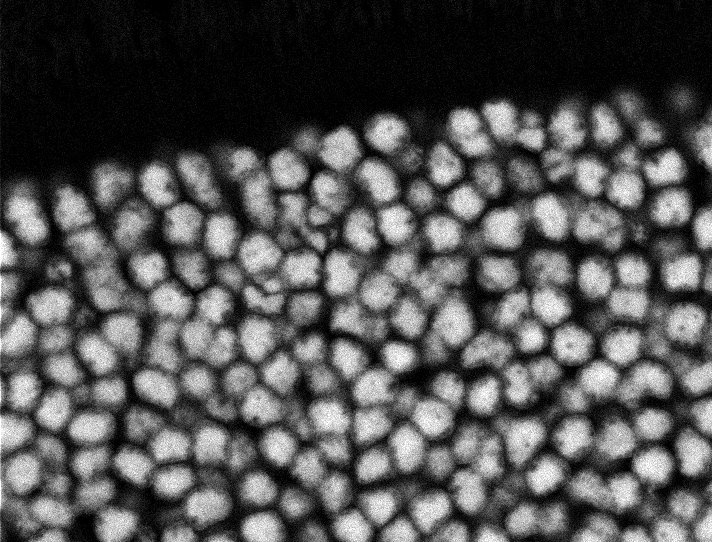

Muscle Cancer